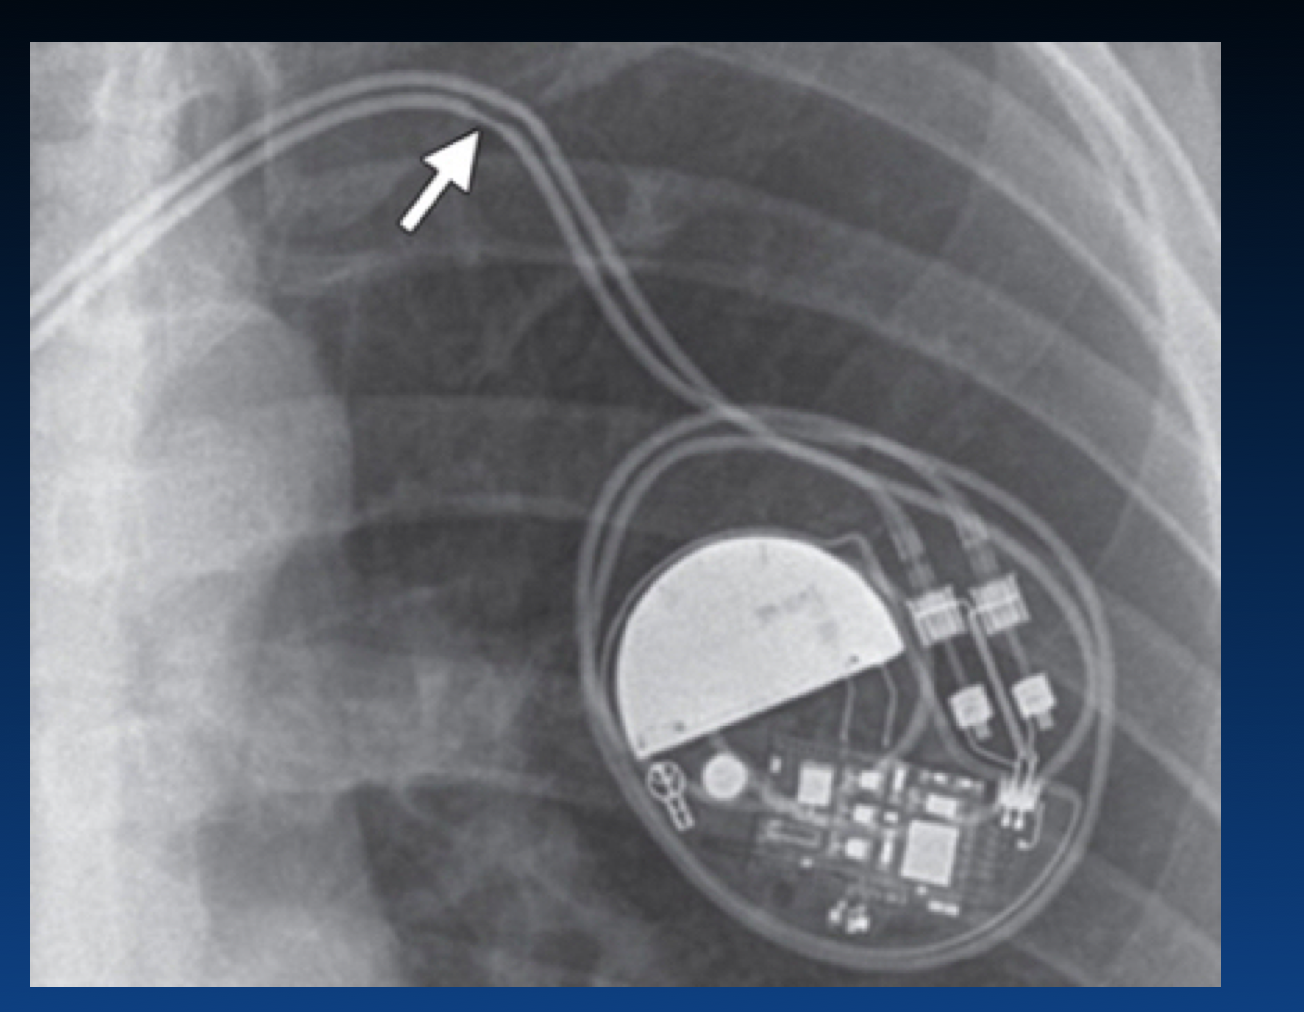

What is shown at the arrow?

Name the Pacemaker/ICD Complication

Misplaced lead

What is Twiddler Syndrome?